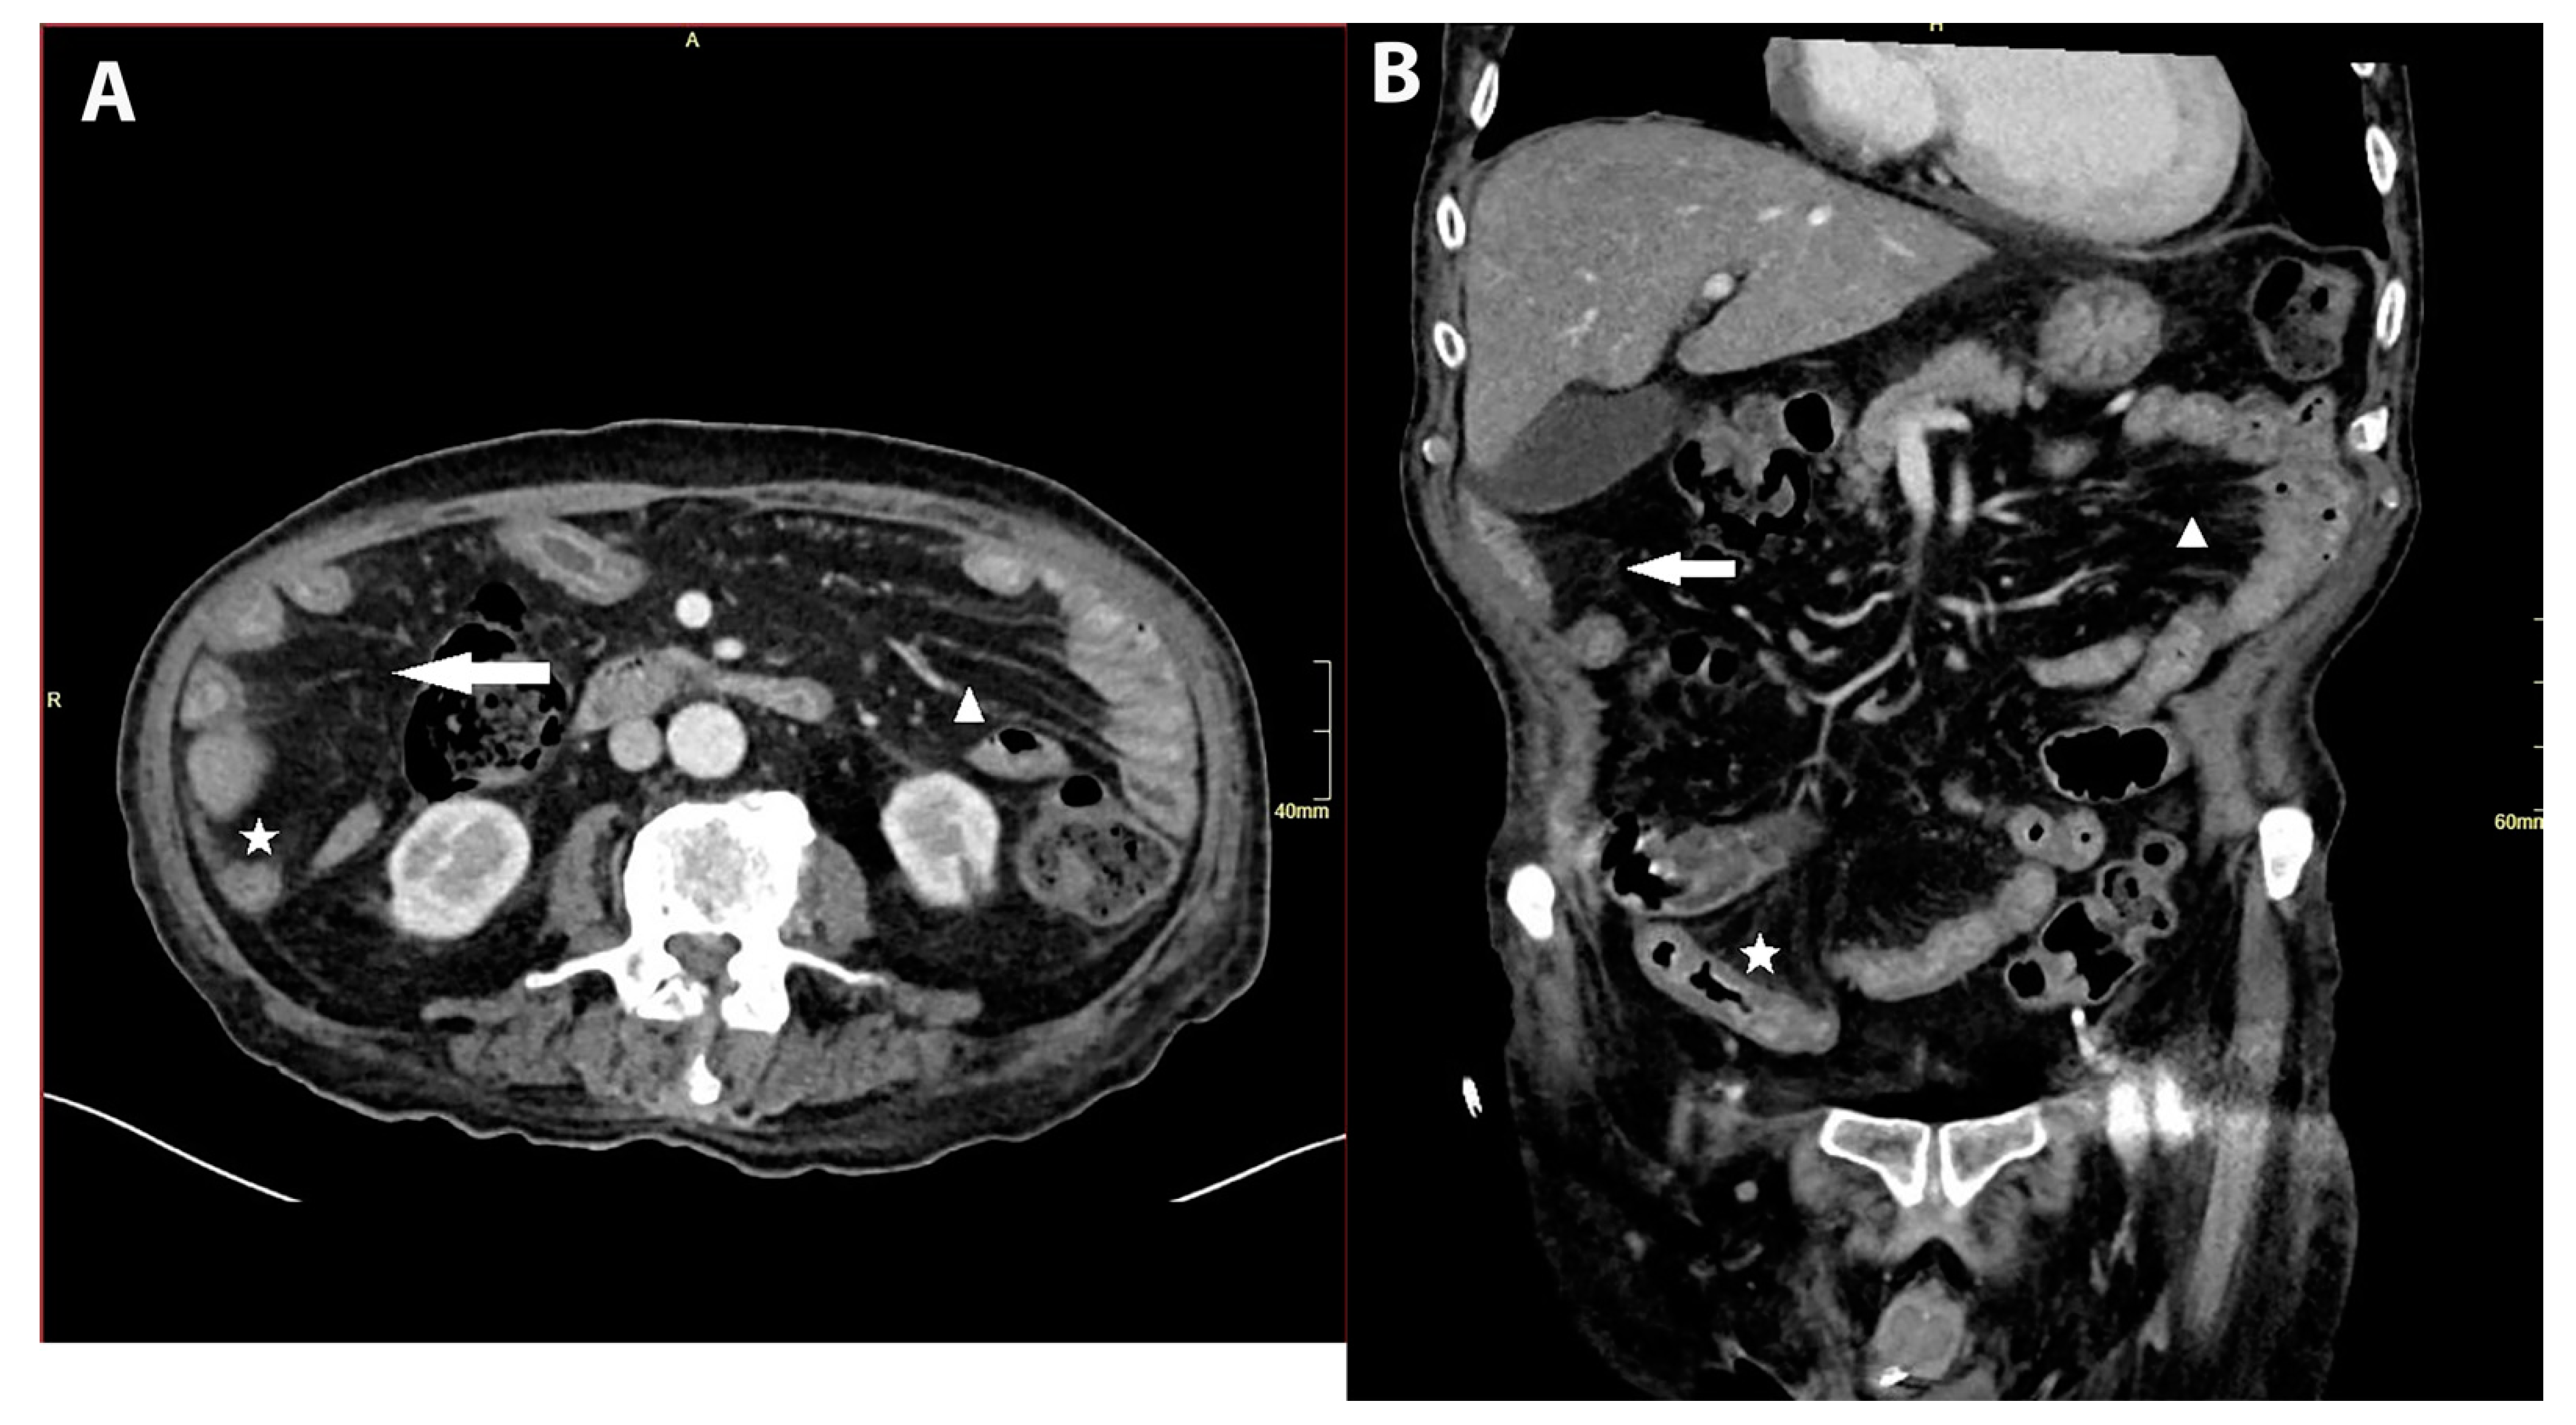

Figure 2. (A,B): Abdominal CT with signs of infectious enteritis. Axial (A) and coronal (B) contrast-enhanced CT images showed signs of an infectious enteritis. The capture shows diffused small bowel wall thickening with mucosal hyperenhancement (asterisk) and perienteric fat stranding (arrow). It also shows mesenteric vessel engorgement (arrowhead). The small bowel was affected entirely from the duodenum to the ileocecal valve. We did not confirm ischemic colitis. Conclusion: CMV infection is usually considered in patients with AIDS, hematological malignancies or after tissue and organ transplantation; however, tissue-invasive CMV disease can also appear in an immunocompromised patient due to long-term corticosteroid therapy.